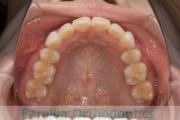

上顎

下顎